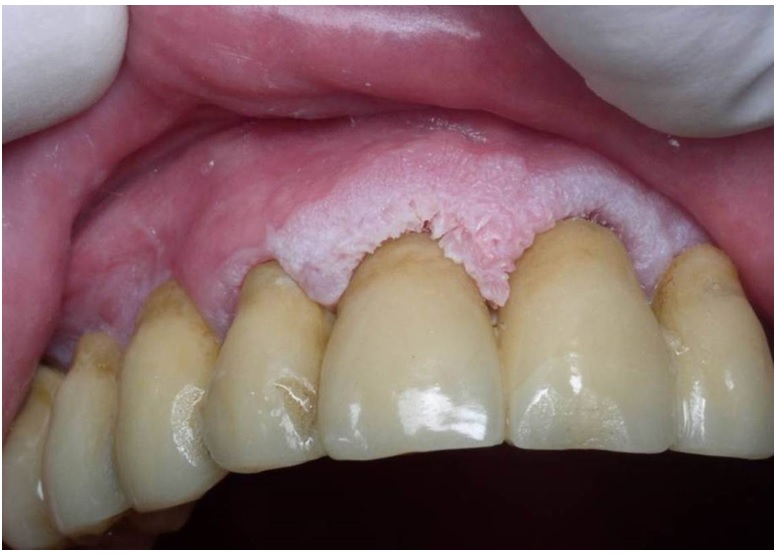

Se caracteriza por ser una lesión eritematosa como una mancha, placa o, en algunos casos, atrofia, que puede ser plana o deprimida, de superficie lisa o con una leve elevación, de bordes bien definidos, usualmente única, no mayor de 1,5 cm, y de aspecto inflamatorio. Se ubica sobre una mucosa habitualmente atrófica, sin presencia de queratina, con una tonalidad rojiza a causa de la fina capa de epitelio que trasluce la microvascularización. Puede o no haber presencia de un componente leucoplásico que, cuando está presente, se denomina eritroleucoplasia (figura 4). Esta lesión, por lo general, es asintomática; sin embargo, algunas veces suele acompañarse con sensación de ardor o dolor (45). Los sitios más afectados son el piso de la boca, el paladar blando, la mucosa yugal, la cara ventral de lengua y las amígdalas (43).

En el borde lateral derecho presenta una lesión tumoral con diagnóstico de carcinoma escamocelular

Fuente: elaboración propia.La forma clínica de la eritroplasia varía según el grado de inflamación que presente y su aspecto granular. Se manifiesta como una lesión de color rojo-aterciopelado de mucosa normal o en algunos casos queratósica, de superficie granular, que sangra con facilidad. Es inusual encontrar en estas lesiones áreas ulceradas, duras y de crecimiento exofítico (46).